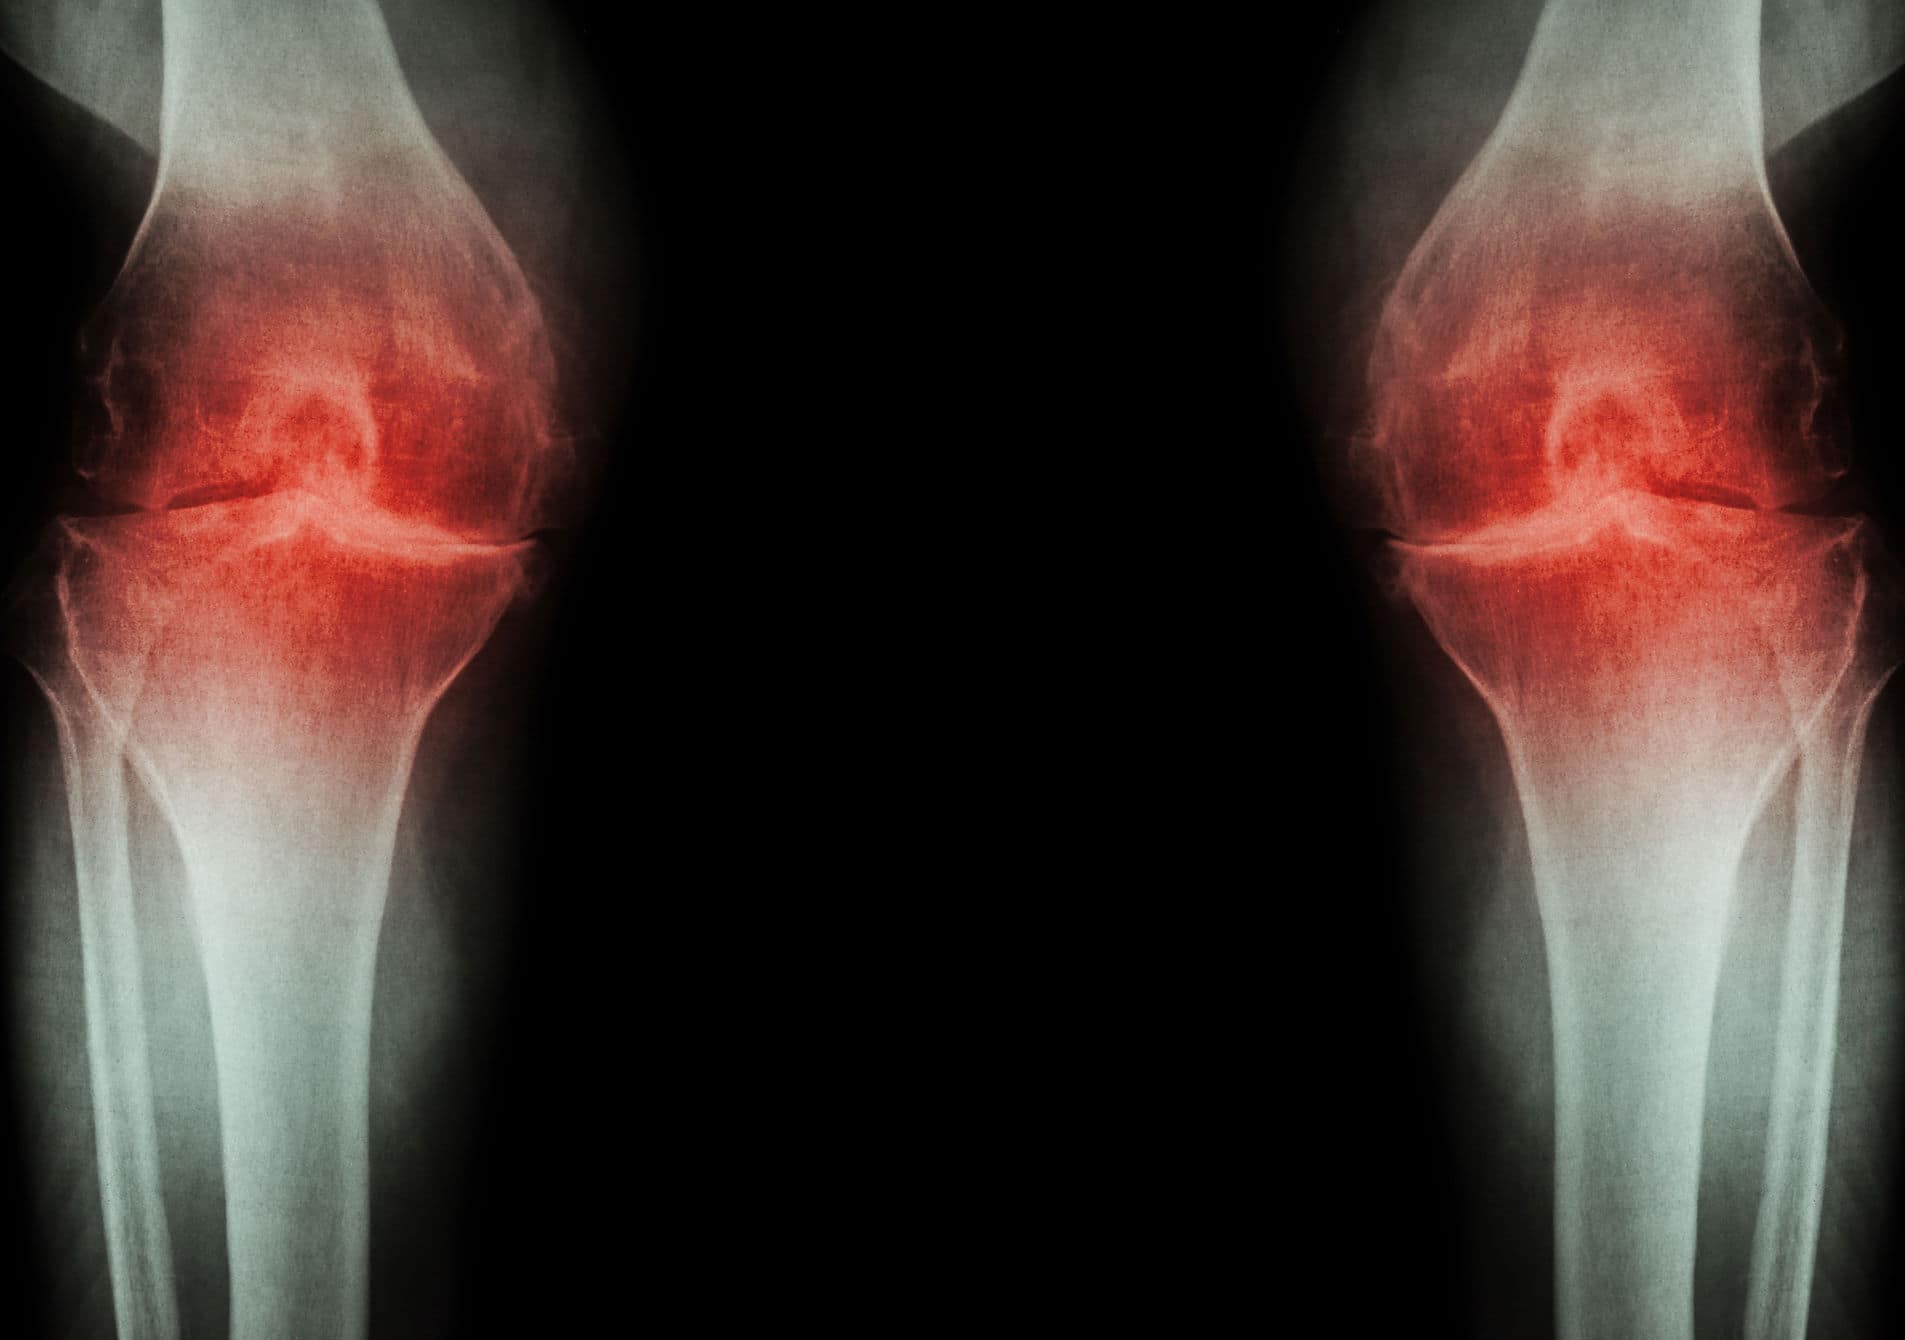

Artroza, osteoartroza ili trošenje zglobova vrlo je česta degenerativna bolest zglobova koja može zahvatiti bilo koji zglob u tijelu. Najčešće se javlja u zglobovima koji nose najveći dio naše težine , dakle artroza koljena, kuka i kralježnice ali pa so najbolj uporabljeni pri vsakodnevnem delu, torej artroza sklepov dlani in prstov. Artroza lahko povzroča tudi vnetje in bolečino v prizadetih sklepih, kar imenujemo osteoartritis. Ljudi zaradi artroze najpogosteje težijo bolove u koljenu. U većini zemalja ova se dva pojma (osteoartroza i osteoartritis) jasno razlikuju, no u engleskom govornom području postoji određena zbrka jer se pojam artroza pogrešno zamjenjuje pojmom osteoartritis čak i u slučajevima kada upala nije prisutna.

Artroza kolena je ena najpogostejših oblik, saj kolenski sklep nosi velik del telesne teže in je vsakodnevno obremenjen.

Artroza nastaje kada se zglobna hrskavica ili njezin dio stanji, a površina postane hrapava. To se događa zbog stalnog opterećenja zglobova i u starosti je gotovo normalna pojava. Naravno, tome mogu pridonijeti otežavajući čimbenici, osobito spol, prekomjerna tjelesna težina i genetske predispozicije. U zdravom zglobu hrskavica koja prekriva površinu kostiju je glatka i klizna, što omogućuje da se kosti u zglobu nesmetano i s minimalnim trenjem pomiču jedna uz drugu. Kod artroze, zbog oštećenja hrskavice trenje je veće, štos vremenom može uzrokovati tegobe. Budući da je hrskavica istrošena i oštećena, u zglobu započinju fiziološki procesi koji pokušavaju popraviti nastalu štetu. Ti procesi mogu promijeniti strukturu zgloba i često omogućiti da on ponovno normalno funkcionira bez boli.S godinama će većina ljudi imati artrozu u zglobovima, no zbog tih mehanizama organizma toga često nećemo biti ni svjesni. Artroza je prisutna kod više od 10 % ljudi mlađih od 40 godina, kod više od 40 % ljudi starijih od 40 godina i kod 60 % ljudi starijih od 65 godina , no samo kod manjeg dijela njih pojavljuju se i bolovi u koljenu.